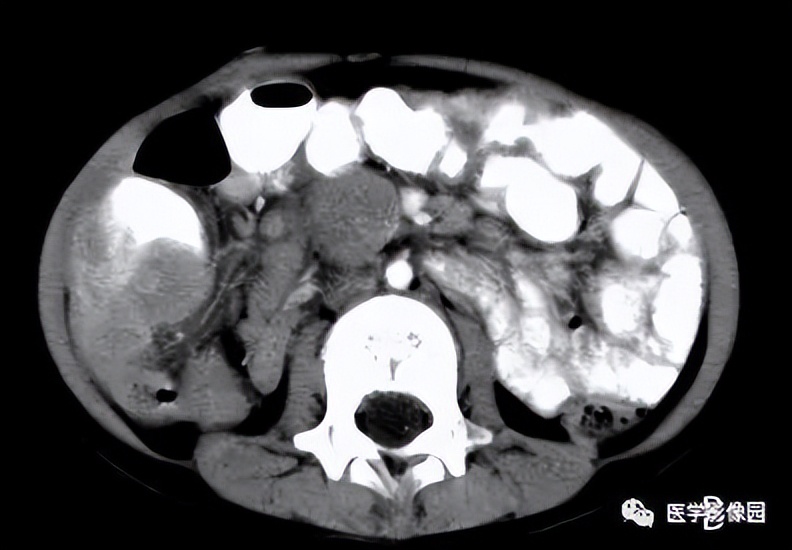

应用海扶刀设备治疗子宫肌瘤对于肌瘤的大小没有特别的限制,只要海扶刀机载超声定位能够看得见的、能够建立安全超声治疗通道的,通常都能够进行消融治疗。

几公分、十几公分,甚至二十几公分的肌瘤,海扶刀设备都可以治疗,并且一般是一次性消融治疗,只有极少数肌瘤特别大的情况可能需要分次消融治疗。